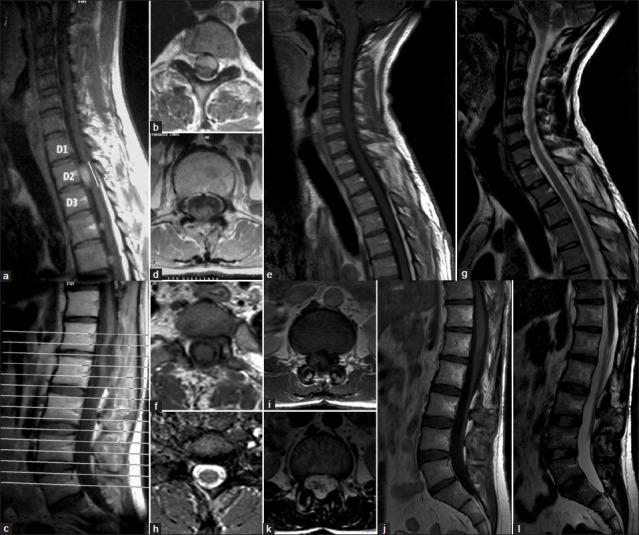

Case 1 was a 30-year-old man with progressive paresthesia and paresis in the lower limbs, urinary sphincter disturbances, gait instability, ataxia, and chronic low back pain with multiple intradural extramedullary lesions at C2-C3, D2-D4-D5, and D12-L1. Case 2 was a 32-year-old man, presented with low back pain and mild paresthesia in the right lower limb. Magnetic resonance imaging (MRI) showed multiple intradural extramedullary lesions with homogeneous enhancement after gadolinium injection at C7, D2, D4, D5, D8, D10, D11, L1, L3, L5, S1, and S2. Complete tumor resection of the approached tumors was archived in both cases. Histological studies confirm myxopapillary ependymomas. Patient's neurologic outcome was good and no residual tumor was present at MRI control at 10 years in case 1 and 12 months in case 2.

病例1为一名30岁男性,出现下肢进行性感觉异常和无力、尿失禁、步态不稳、共济失调以及慢性下背痛,在C2 - C3、D2 - D4 - D5和D12 - L1处有多个硬膜内髓外病变。病例2为一名32岁男性,表现为下背痛和右下肢轻度感觉异常。磁共振成像(MRI)显示在C7、D2、D4、D5、D8、D10、D11、L1、L3、L5、S1和S2处有多个硬膜内髓外病变,注射钆后呈均匀强化。两例均对所累及的肿瘤进行了完整切除。组织学研究证实为黏液乳头型室管膜瘤。病例1在10年的MRI复查时患者神经功能预后良好且无残留肿瘤,病例2在12个月时情况相同。